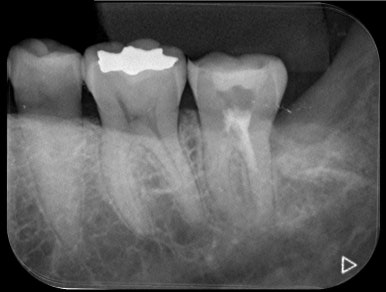

🔧 근관 내 소독 + 충전 마무리 후

| 전 | 후 |

→ 통증 소실, 저작 시 불편감 사라짐

→ 지르코니아 크라운으로 마무리 수복